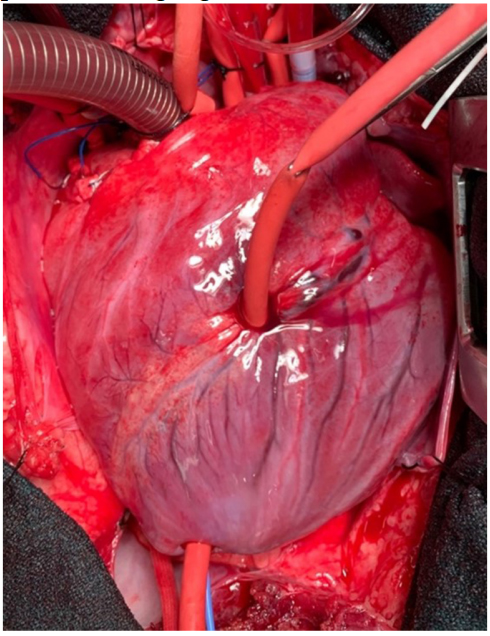

An early study in 2005 comparing diazoxide to control in a porcine model found that diazoxide did not provide cardioprotection (infarct size and systolic function) after myocardial ischemia[133]. The authors acknowledged that their results were incongruent with others’ findings and postulated that this could be due to preconditioning effects of anesthetics or an incorrect dose of diazoxide. Recent studies have been more promising. In an isolated mouse heart model, adding diazoxide to cardioplegia led to improved diastolic function following a period of global ischemia[134].Two subsequent studies were conducted in swine models. In the first, swine treated with hypothermic, hyperkalemic cardioplegia with diazoxide (single dose) prior to a 2-h global ischemic period were found to have improved systolic and diastolic ventricular function compared to cardioplegia alone [Figure 2][135]. In the second, swine underwent 30 min of occlusion of the left anterior descending artery prior to 2 h of global ischemia protected with cardioplegia or cardioplegia with diazoxide (dosed every 20 min) [Figure 3][136]. Compared to cardioplegia alone, animals that received diazoxide had decreased myocardial stunning and shortened time to separate from cardiopulmonary bypass [Figure 4][136]. These studies provided some of the most convincing preclinical data to date that diazoxide will be beneficial as an additive to cardioplegia in humans undergoing cardiac surgery requiring global ischemia. It is important to acknowledge the limitations of the translational models that have been widely used to study KATP channels and cardioprotection. These models may not provide sufficient confidence to translate to human pathophysiology. These limitations highlight the importance of randomized clinical trials in humans before widespread adoption.

Figure 3. Photograph of porcine heart in the Lawton laboratory following cannulation for cardiopulmonary bypass, placement of left ventricular pressure catheter, and placement of left anterior descending tourniquet for regional ischemia prior to a longer global ischemia in a model simulating clinical cardiopulmonary bypass with an acutely injured heart. Regional ischemia is evident in this porcine heart after occlusion of the left anterior descending coronary artery for 30 min for regional ischemia. Subsequently, the heart will be exposed to two hours of global ischemia protected with cardioplegia with or without diazoxide, followed by reperfusion[136]. This model simulates the clinical situation of a patient presenting to the operating room with ongoing ischemia prior to a coronary revascularization procedure with prolonged global ischemia[136]. This figure is used with permission from Elsevier (obtained December 12, 2023, license number 5686380805849)[136].